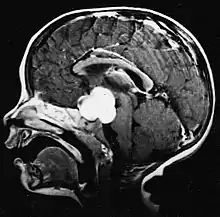

Glioblastome

Les tumeurs des cellules gliales les plus courantes et les plus malignes sont les glioblastomes. Ils consistent en une masse hétérogène de cellules d'astrocytome peu différenciées principalement chez l'adulte. Ils surviennent généralement dans les hémisphères cérébraux, plus rarement dans le tronc cérébral ou la moelle épinière. Sauf dans de très rares cas, comme toutes les tumeurs cérébrales, elles ne s'étendent pas au-delà des structures du système nerveux central.

Le glioblastome peut provenir d'une forme diffuse (II. grade) ou un astrocytome anaplasique (III. grade) développer. Dans ce dernier cas, il est dit secondaire. Cependant, lorsqu'elle survient sans antécédent ni signe de malignité antérieure, on parle de maladie primaire. Les glioblastomes sont traités par chirurgie, radiothérapie et chimiothérapie. Ils sont difficiles à guérir et rares sont les cas qui survivent au-delà de trois ans.

Sur-L'IRM montre une tumeur intracrânienne comme une lésion massive qui peut devenir plus luminescente après utilisation du produit de contraste. Cependant, il y a toujours une anomalie de signal dans -L'imagerie par résonance magnétique, qui indique la présence d'une néoplasie ou d'un œdème vasogénique. Habituellement, une luminescence accrue (amélioration du contraste) indique une tumeur d'un grade supérieur de malignité. Un anneau de contraste est caractéristique du glioblastome, avec la partie luminescente correspondant à la partie vitale de la tumeur maligne, et la plus foncée - zone hypointense correspondant à une nécrose tissulaire.